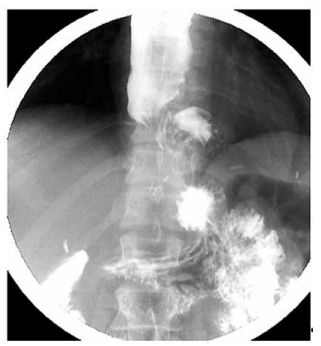

Paciente de 45 anos, submetido à miotomia de Heller com fundoplicatura parcial (dor) por acalasia há oito meses, evoluiu com melhora inicial da disfagia, mas retornou com piora progressiva dos sintomas nos últimos dois meses. A endoscopia digestiva alta mostrou esôfago dilatado com acúmulo de conteúdo alimentar e resistência à passagem do aparelho na transição esofagogástrica. A manometria esofágica de alta resolução não pôde ser realizada, pois não foi possível o posicionamento adequado do cateter manométrico na junção esofagogástrica. Realizou o esofagograma apresentado a seguir:

(Arquivo pessoal; imagem usada com autorização)